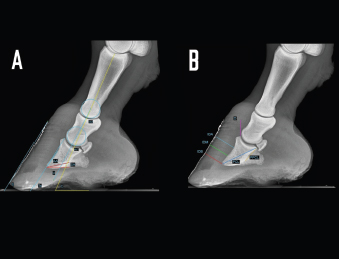

A series of 17 linear and angular, direct and derived radiometric parameters were evaluated in all 56 forefeet, for LM and DPa views (Fig. 1), according to the literature (Collins et al., 2011). A detailed description is given in Table 1. These parameters evaluate the anatomical relationship between the osseous structures of the foot, define their relationship with the hoof capsule, and characterize the morphometric appearance of the distal phalanx in a normal foot (Collins et al., 2011).

Fig. 1. LM radiographs of a normal donkey foot showing the angular (A) and linear (B) parameters established using Osirix DICOM Viewer (Pixmeo SARL, Switzerland). (A) Key: SA, angle of solar aspect of the distal phalanx. Ts, dorsal angle of the distal phalanx. AA. S, dorsal hoof wall angle. U, angle of proximal phalanx. C, angle of middle phalanx. Dorsal is to the left of image and palmar is to the right. (B) Key: IDA, integument depth (proximal site). IDM, integument depth (mid-dorsal site). IDB, integument depth (distal site). D, distal displacement of the distal phalanx. PCL, and PPCL. Dorsal is to the left of image and palmar is to the right.